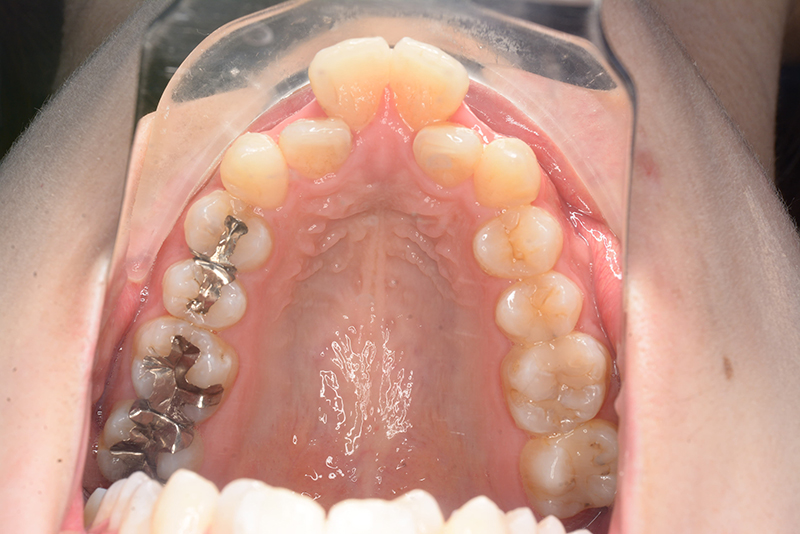

初診時

FP・IOP

口腔内所見 over jet 11.5mm、over bite 5.5mm、右側臼歯関係Full ClassⅡ級、左側end onⅡ級、上顎顎歯列はテーパー型であり、上顎中切歯は押し出されるように大きく唇側傾斜していた。下顎前歯部は叢生を呈しており、左下5は歯冠長が短く半埋伏していた。

パノラマ所見 上下顎両側第三大臼歯は埋伏していた。下顎右側大臼歯から犬歯まで近心傾斜し、左側においては左下5を境に大臼歯は近心傾斜、近心の歯は遠心方向へ傾斜が認められた。